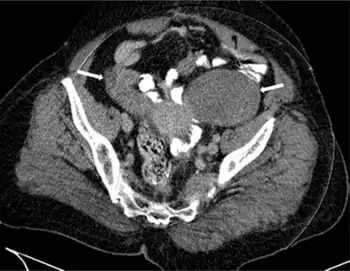

All these symptoms are non-specific and can also arise with a range of problems other than cancer, and a diagnosis can only be made following confirmatory investigations such as computed tomography (CT) scans, laparotomy and/or a biopsy of the ovary.

In terms of the diagnosis of krukenburg tumors the following is done:[8]

- CT scan

- Ultrasound

- CA-125 Test (elevated)